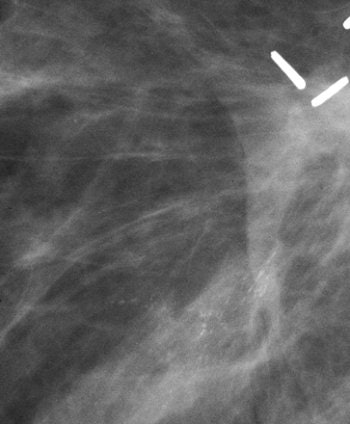

| A 50-year-old breast cancer patient with recurrence presenting as microcalcifications three years after treatment. Magnification of mediolateral oblique view of lumpectomy site shows clips and scar. Note new pleomorphic microcalcifications nearby. These microcalcifications were ductal carcinoma in situ with microinvasion located 2 cm from lumpectomy site. Pinsky RW, Rebner M, Pierce LJ, Ben-David MA, Vicini F, Hunt KA, Helvie MA, "Recurrent Cancer After Breast-Conserving Surgery with Radiation Therapy for Ductal Carcinoma in Situ: Mammographic Features, Method of Detection, and Stage of Recurrence" (AJR 2007; 189:140-144). |